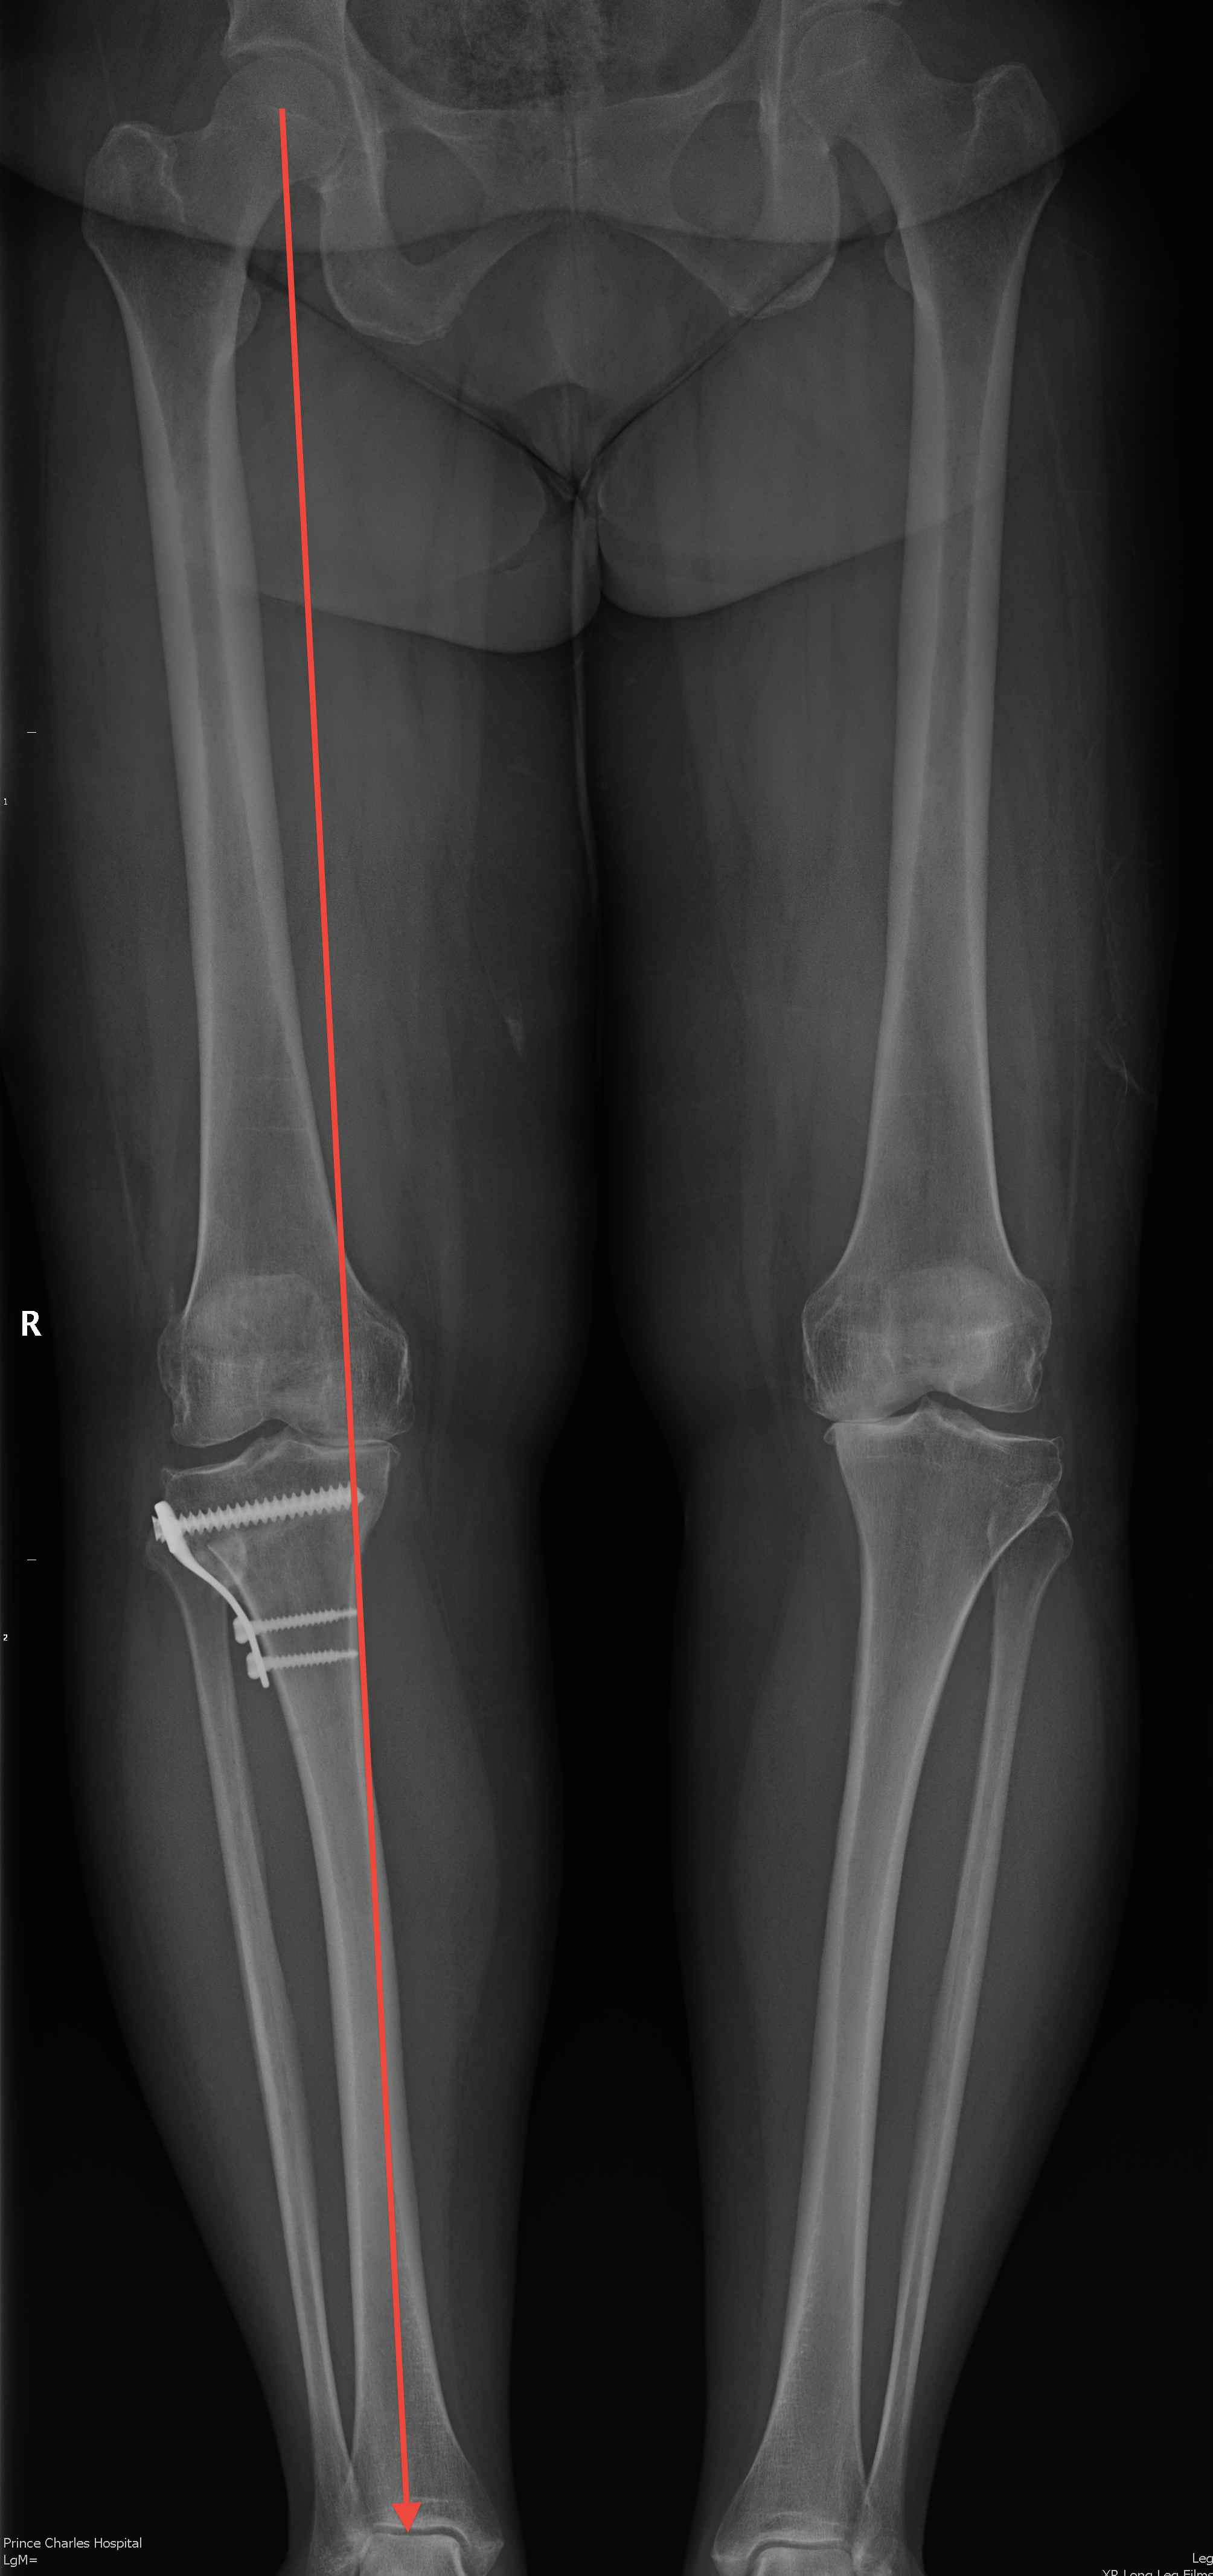

Check correction

- drop rod

- Fujisawa point